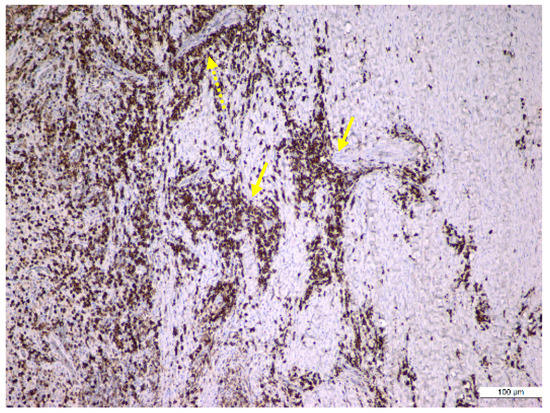

| Histological Lesions | ||||

| Periapical Granuloma | Periapical Granuloma with Cystic Potential | Periapical Cyst | p-Value | |

| Cases, n (%) | 15 (50) | 3 (10) | 12 (40) | |

| Periapical Status Index, 5/4/<3, n (%) | 3/4/8(20/26.7/53.3) | 1/1/1(33.3/33.3/33.3) | 9/2/1(75/16.7/8.3) | 0.013 |

| MSMT, mm, (mean ± SD) | 1.2 ± 0.4 | 2.6 ± 0.7 | 3.7 ± 0.8 | 0.002 |